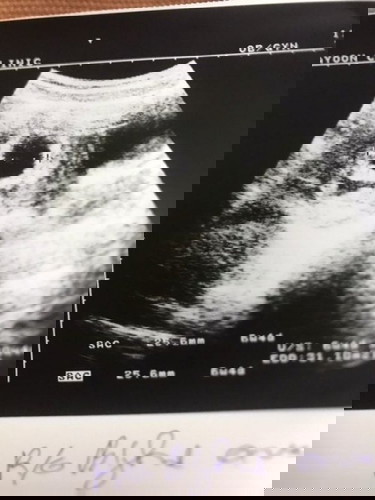

หมอบอกมีสิทธิ์ท้องลมค่ะ หาหมอ3อาทิตย์ติด อยู่ๆก็มีถุงเพิ่มขึ้นมาข้างล่าง แบบนี้เป็นยังไงคะ หมอบอกถ้าไม่ท้องลมก็ท้องแฝดค่ะ